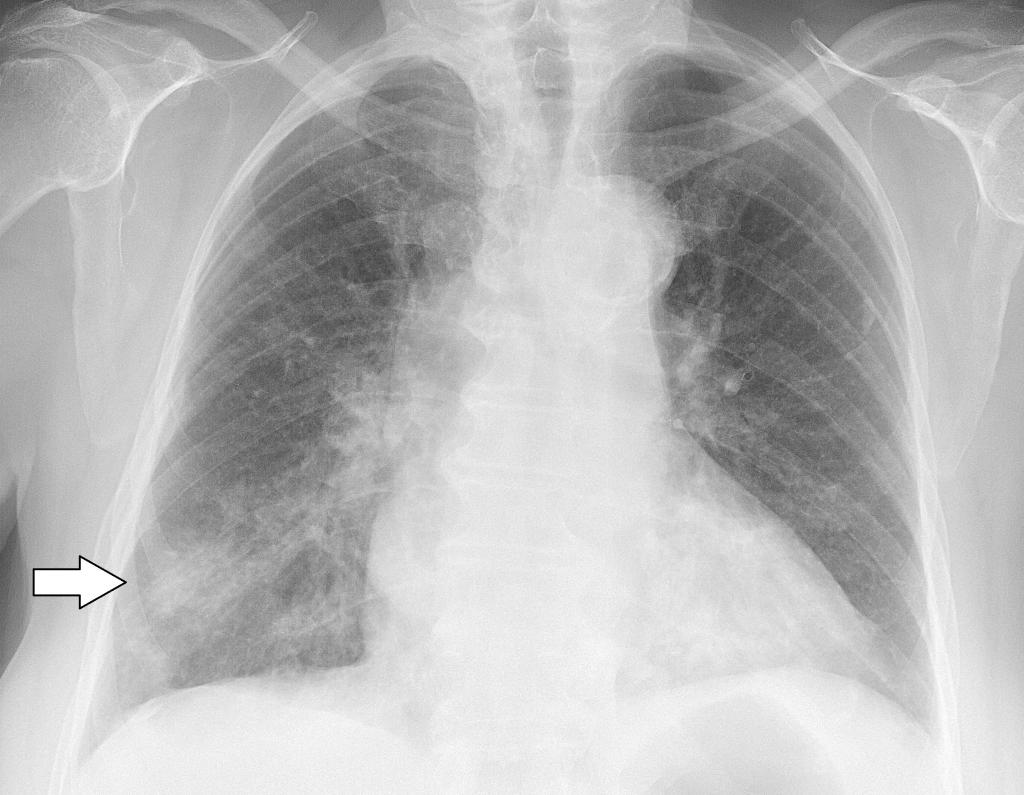

При рентгеновском излучении лёгких, поражённых коронавирусной инфекцией, наблюдаются затемнения в нижней части органа (на снимке обозначаются белыми пятнами). Пятна называются симптомом “матового стекла”. На рентгене видны пятна, которые обуславливаются наличием жидкости в лёгких.

Симптом “матового стекла” в легких

Симптом “матового стекла” проявляется у больных на фоне поражения лёгких вирусом. Так как дыхательный орган подвергается серьёзным изменениям, в нём появляются зоны повреждений.

Снижается плотность лёгочной ткани. В поражённом участке проявляется умеренно-сниженная воздушность, главным признаком выступает видимость сосудов лёгких и стенок бронхов.

Заметить данный симптом на рентгене сложно, поэтому требуется дополнительно сделать компьютерную томографию.

Типичные признаки проявления симптома “матового стекла”:

- стенки и структура бронхов чётко проглядываются;

- видны затемнения;

- сохраняется сосудистый рисунок;

- повышается прозрачность лёгочной ткани.

Ниже представлены фото, как выглядит симптом “матового стекла” на рентгене и компьютерной томографии: